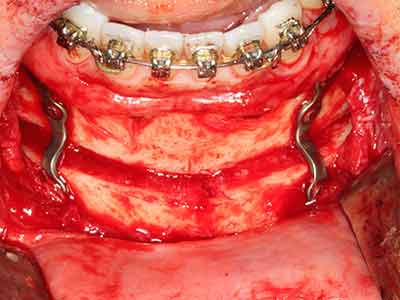

Bei der Knochenblockentnahme zeigen sich weitere Vorteile für die Piezochirurgie: Neben der bereits beschriebenen hohen Präzision bei der Osteotomie stellt sich gerade die Verwendung der dünnen Sägespitzen als besonders materialschonend heraus. Bei der Verwendung insbesondere von Lindemannfräsen sind mit deutlich höheren Entnahmeverlusten durch die dickere Instrumentenspitze zu rechnen (Lakshmiganthan, Gokulanathan et al. 2012). Die insbesondere bei retromolar entnommenen Blocktransplantaten notwendige basale Abtrennung wird durch speziell hierfür vorgesehene rechtwinklige Sägen erleichtert, so dass die Piezochirurgie als präzises, übersichtliches und sicheres Verfahren zur retromolaren Knochenblockgewinnung angesehen wird (Happe 2007) (Abb. 1-12).

Knochengewebe ist nicht nur rein mineralisch, sondern auch in wesentlichen Anteilen aus Kollagenfasern aufgebaut. Dies gewährleistet neben einer guten Druckfestigkeit eine gewisse Flexibilität, welche für die Durchführung von Augmentationen genutzt werden kann. Bei der klassischen Expansionsplastik im Sinne eines Bone Splittings wird der atrophierte Kieferkamm in seiner Längsachse gespalten und nach Erreichen einer ausreichenden Osteotomietiefe vorsichtig aufgedehnt (Abb. 13-16), idealerweise ohne den Kiefer wesentlich zu deperiostieren (Brugnami, Caiazzo et al. 2014, Stricker, Fleiner et al. 2014). Bewährt haben sich Schrauben- und Plattensysteme mit zunehmender Expansionsdistanz, um die beiden Knochenlamellen unterhalb der Bruchschwelle voneinander zu distanzieren. In der Regel werden Restknochenbreiten von mindestens 3-4 mm gefordert (Chiapasco, Zaniboni et al. 2006), um eine ausreichende Flexibilität und knöcherne Bedeckung der einzubringenden Implantate zu gewährleisten. Ggf. kann eine ein- oder beidseitige vertikale Entlastungsosteotomie die Flexibilität verbessern. Als Alternative zur klassischen Technik wurde eine Kombination mit weiteren augmentativen Techniken vor allem auf der bukkalen Seite beschrieben.

Mittels Piezosägen erfolgt die Anlage des Splittings besonders schonend und ohne wesentliche Dimensionsverluste, so dass sich keine signifikanten Unterschiede von Implantaten im gesplitteten Kiefer im Vergleich zum nicht defizitären Alveolarkamm gezeigt haben (Chiapasco, Zaniboni et al. 2006, Danza, Guidi et al. 2009). Gerade beim lokal begrenzten und tiefen Splitting ist jedoch stets auf eine ausreichende Wasserkühlung zu achten, um thermische Belastungen in den apikalen Osteotomiebereichen zu vermeiden.

Abb. 1: Präparation eines ent-sprechenden Knochendeckels mit dem Piezomed.

Abb. 13: Bei diesem 52-jährigen Patienten ist bei 4 mm UK-Restknochenbreite während des Bone Splittings auf eine ausreichende Wasserkühlung zu achten.

Abb. 14: Einbringung von vier konischen RSX-Implantaten (Bego Implant Systems, Bremen).